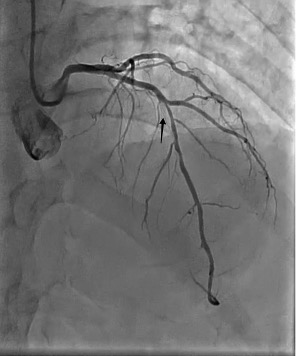

A 72-year-old male underwent elective percutaneous coronary intervention (PCI) for a significant stenotic lesion in the left anterior descending (LAD) artery (Figure 1 white arrow, Video 1).

A wire was placed in the diagonal branch prophylactically to preserve side branch patency during main vessel stenting. After successful deployment of a drug-eluting stent (DES) in the LAD, the side branch wire was withdrawn. However, a radiopaque segment remained within the side branch, while the remaining wire fractured and became entrapped behind the stent struts (Figure 2 [black arrows], Video 2).

Final angiography confirmed TIMI-3 flow with no dissection, perforation, or distal embolization; the wire in the side branch remained in place at the end of the procedure (Figures 2 [white arrow], 4A-C, 5, Video 6).